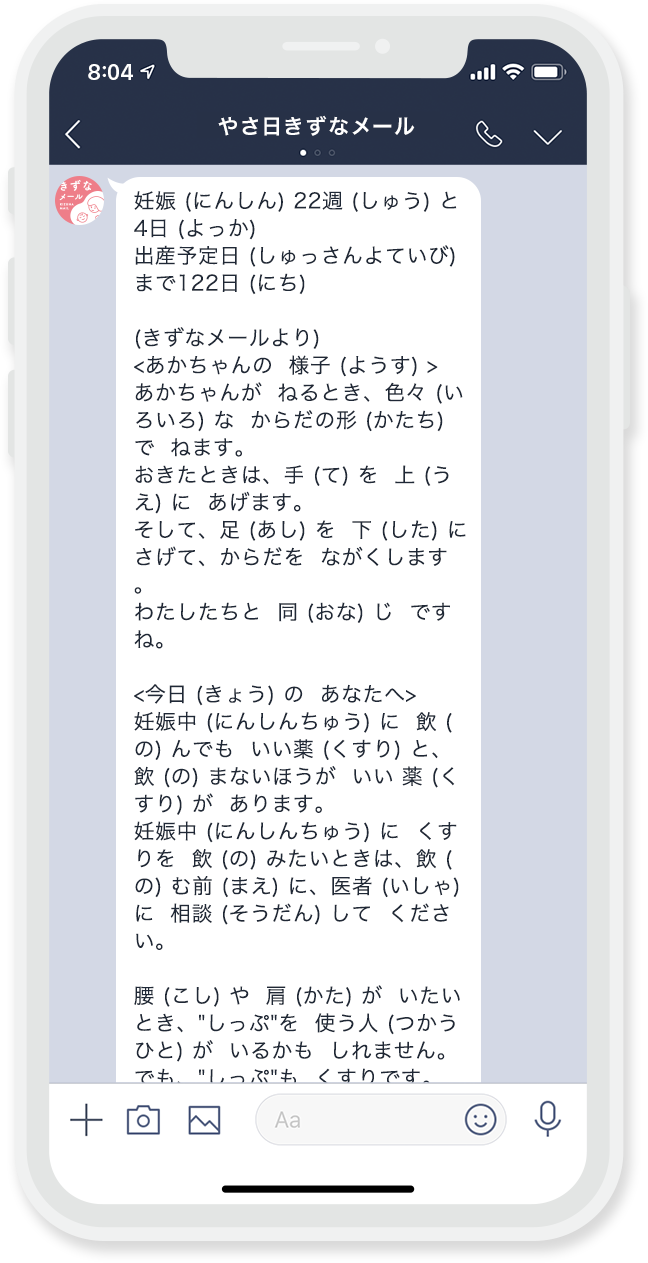

「きずなメール やさしい日本語版」は、

日本に住む外国人の方を対象に、

孤育てを防ぐセーフティネット強化を目的として

2020年11月から制作がはじまりました。

医療監修者と相談しながら「きずなメール」原文を短くし、それをやさしい日本語へ翻訳しました。

最終的な医療監修を行いました。仕上げにボランティアさんに協力頂き、原稿内の漢字にルビ(ふりがな)を振り、「きずなメール やさしい日本語版」が完成しました。

多くの方のご支援ご協力を得て、2022年2月、

ついに原稿が完成しました。

「きずなメール やさしい日本語版にほんごばん」

日本にほんに 住すむ外国人がいこくじんの みなさんへ。

LINEや メールから、やさしい日本語にほんごで

書かいた 情報じょうほうを 送おくります。